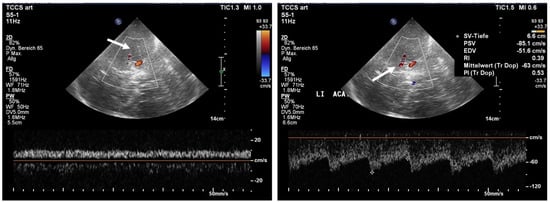

Case Report Continued